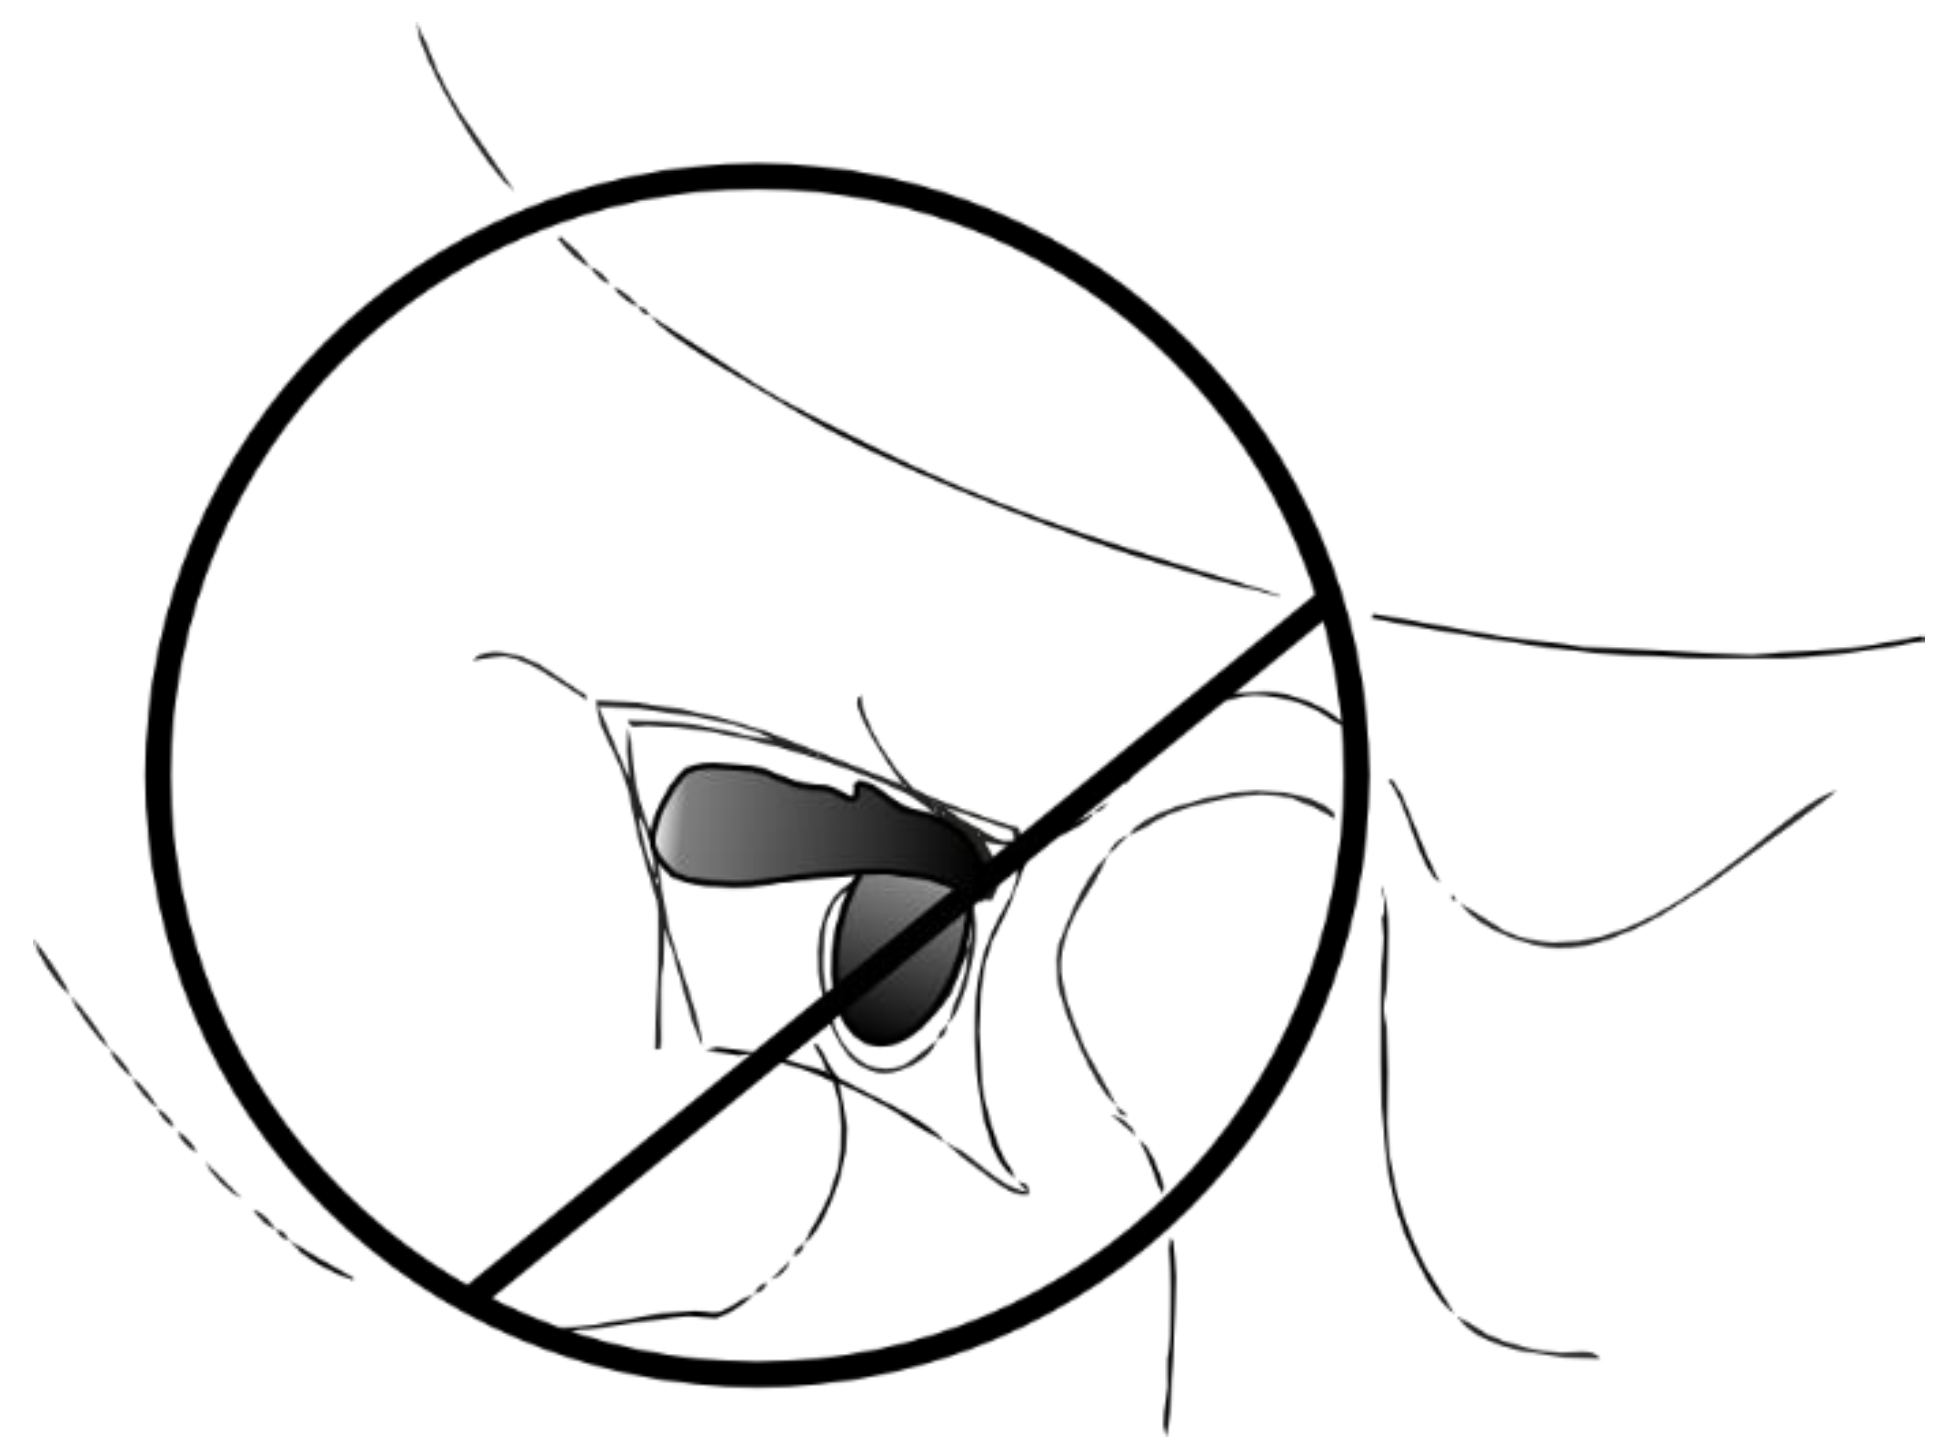

Figure 9.

URCOTEBS_δ is pathognomonic for the state of disease of the D-Organ, equivalent to the state of disease of the ME mucosa − Certain event P(E) = 100%.